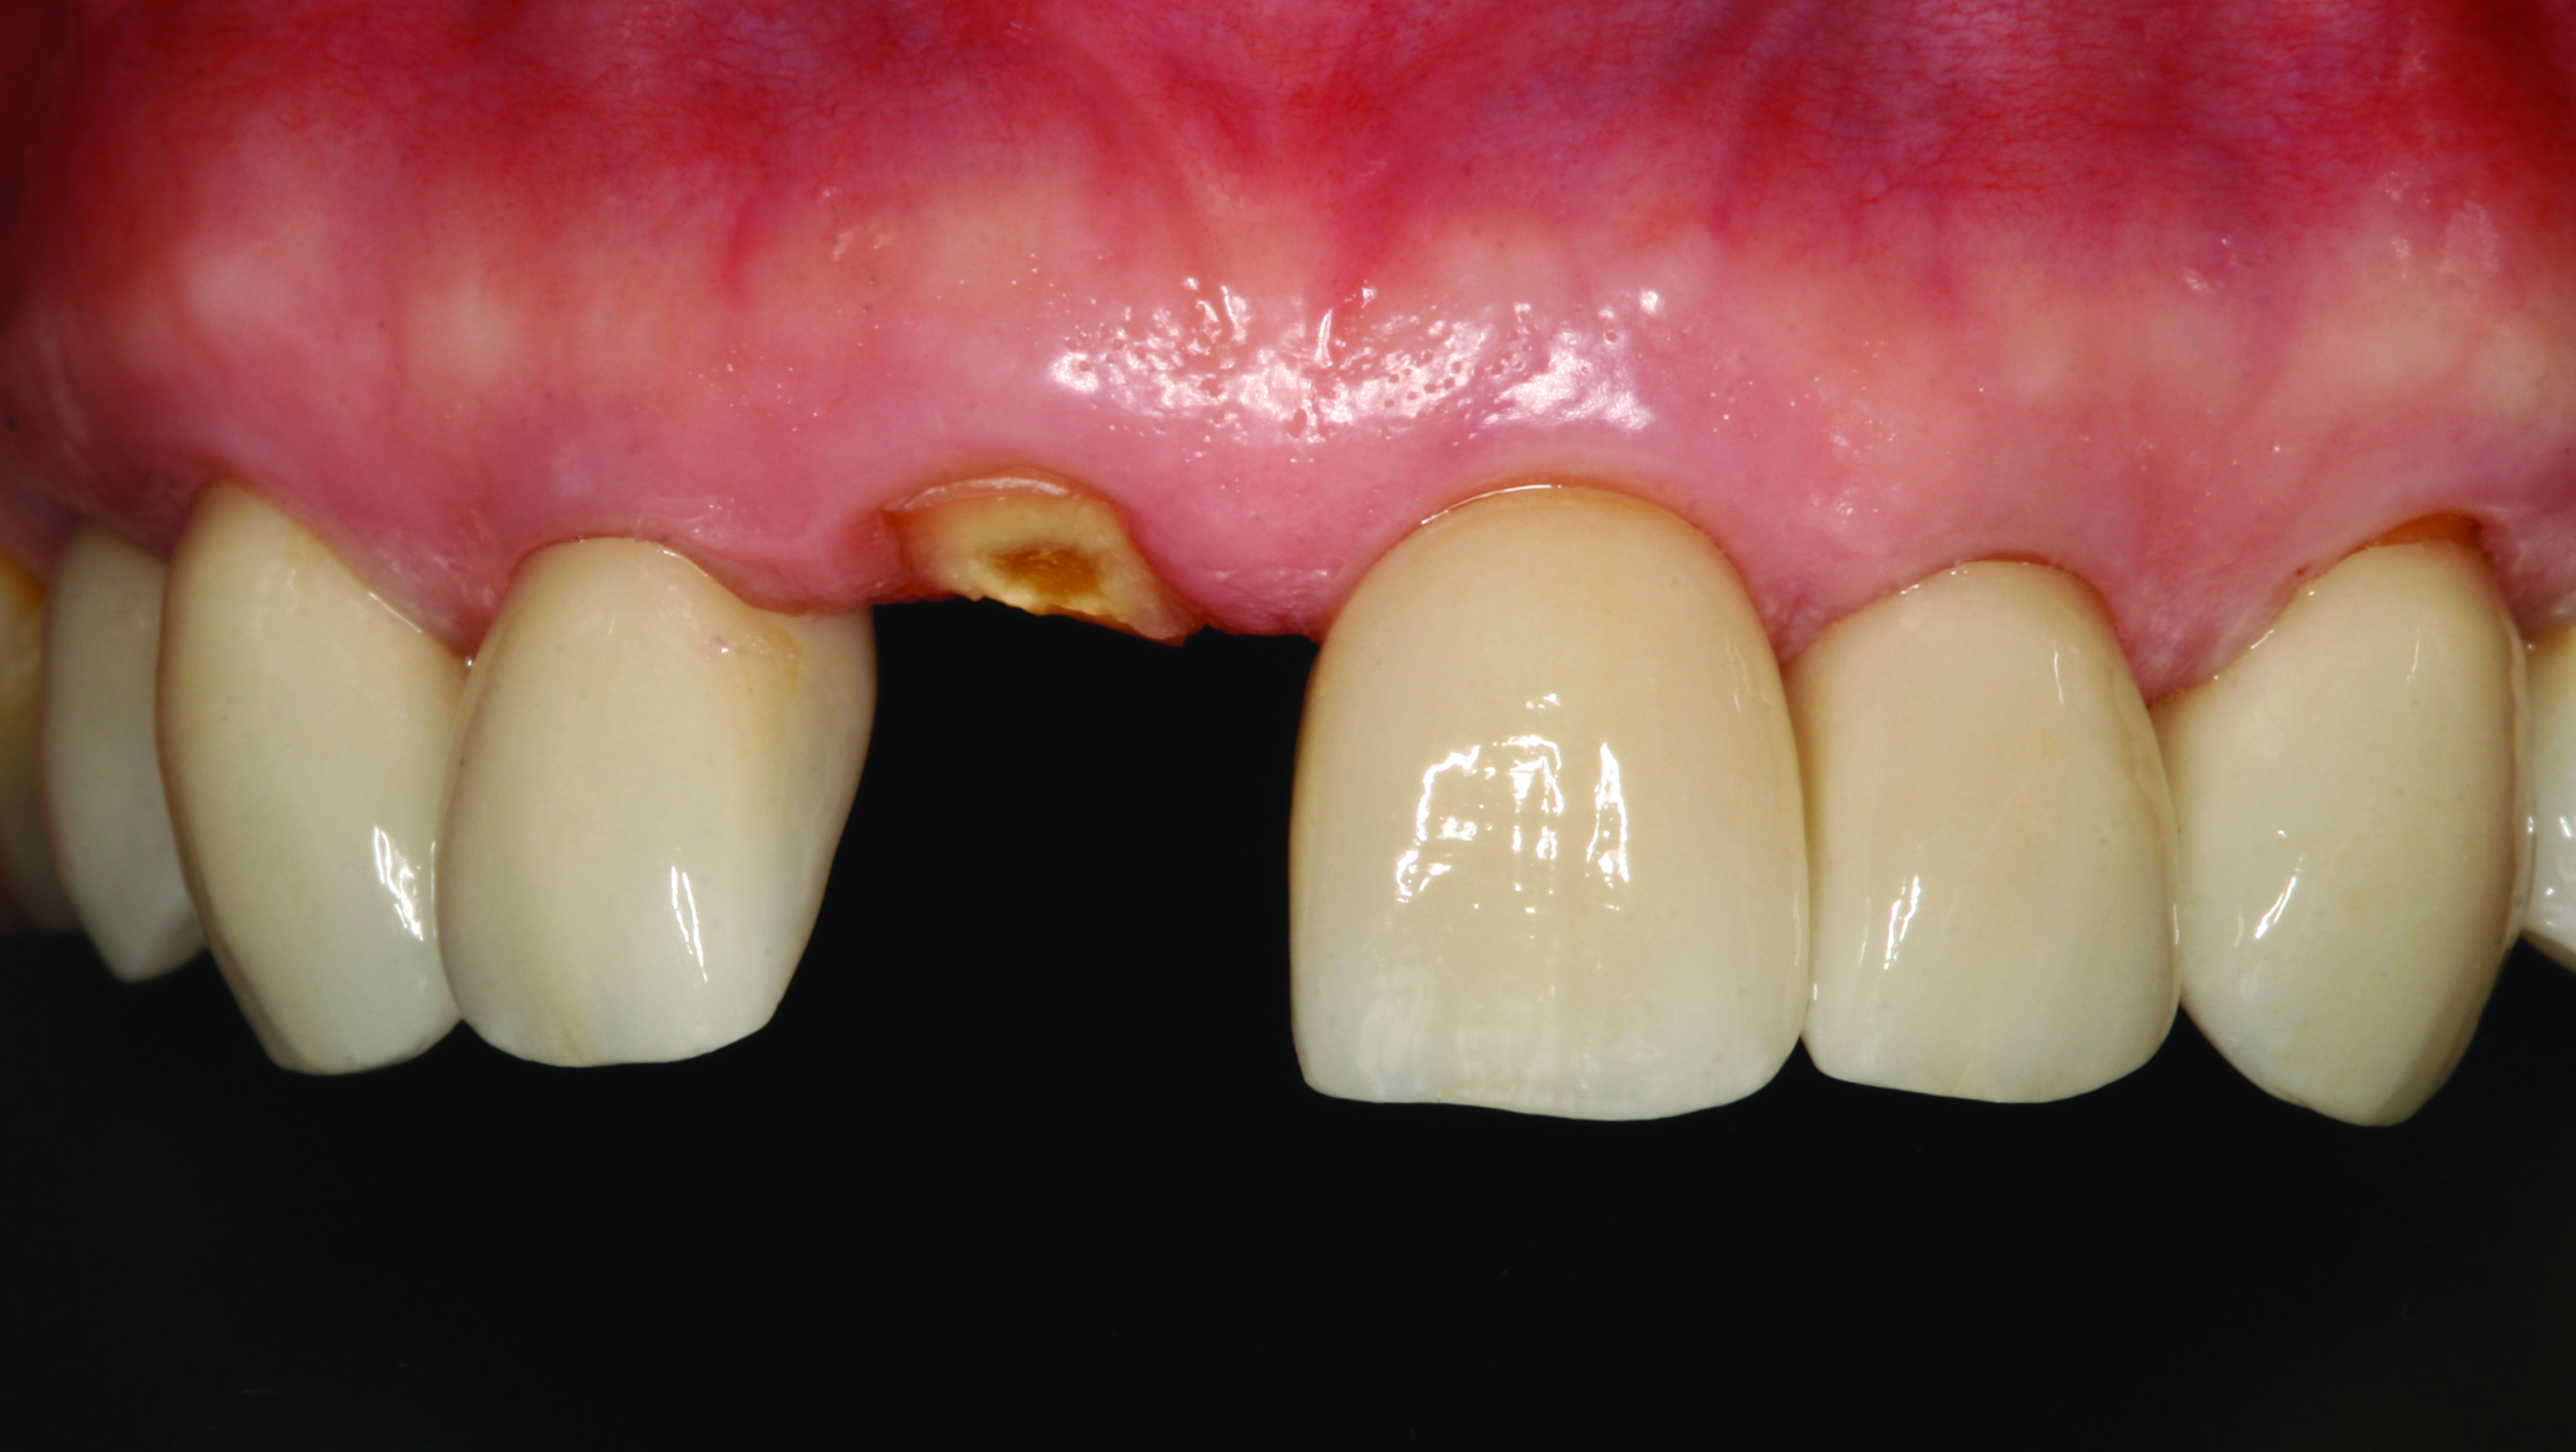

A 62-year-old woman presented on emergency, reporting having fractured her right central incisor (Figure 1). The area was asymptomatic and demonstrated no problems other than the embarrassment associated with the loss of her front tooth. Diagnostic records were made and an Essix retainer (essix.com) was fabricated to help alleviate her immediate esthetic concerns. Due to the lack of tooth structure incisal to the gingiva, the prognosis of the tooth was very guarded. Various options to restore this area were presented to the patient, leading to her ultimate choice of a dental implant. A diagnostic CBCT scan of the patient was attained and the patient left the office wearing the retainer.